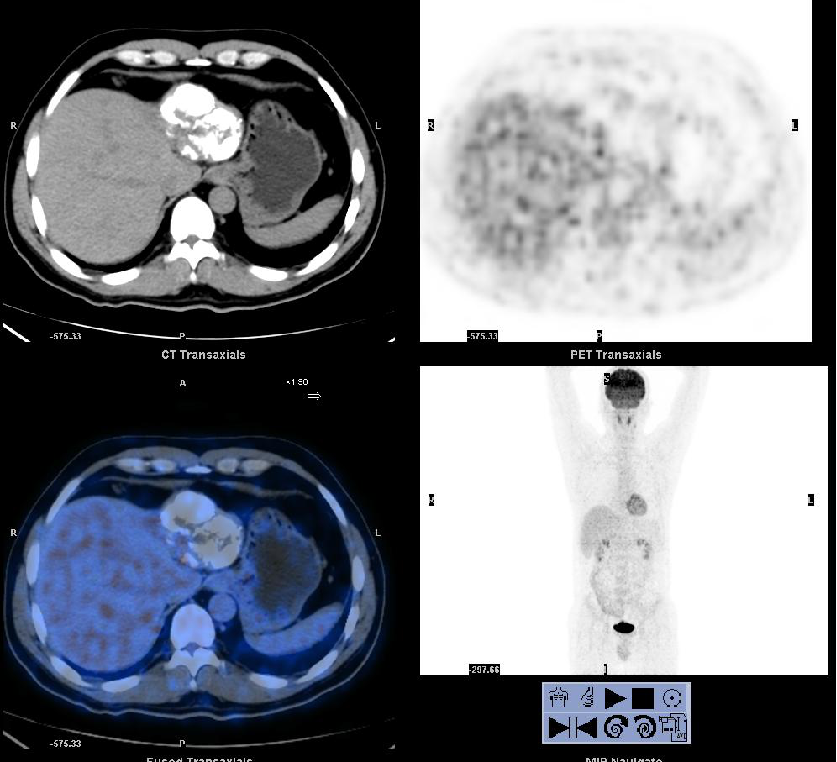

现病史:2011年01月4日于当地医院行PET/CT: 1. 肝左外叶肝癌并肝门区淋巴结转移,2. 下腔静脉及右心房结癌栓,考虑为”原发性肝癌“。

影像学检查:

2011-01-06我院上腹部CT:

肝左叶巨块型肝癌(13.8cm×9.1cm),伴肝右后叶子灶,门静脉左支、肝左静脉及下腔静脉内癌栓。

PET/CT:见肝左叶病灶边缘代谢活跃区。

2012-02-22(第二次消融后2个月)复查PET/CT:肝脏病灶代谢未见异常。AFP:3.52 ng/ml。

2012-06-29(第二次消融)后6个月 复查PET/CT:肝脏病灶代谢未见异常。AFP:2.74 ng/ml。

PET/CT在肝癌疗效评价中的作用:

无论是碘油沉积区还是非碘油沉积区都可能有残留病灶存在。

PET/CT对介入治疗后的残留病灶探测具有较高的灵敏度,可以用于介入治疗后的疗效评价。

其对判断肿瘤残留及指导消融治疗较增强CT检查具有更大的优势。